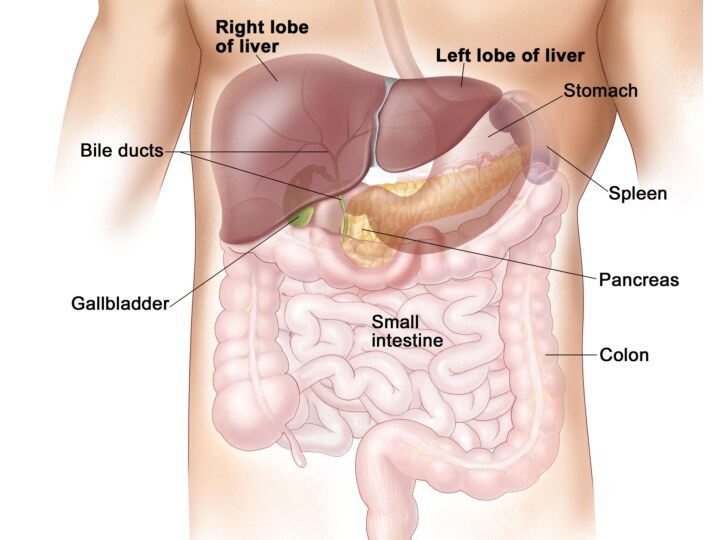

Анатомия и особенности Гартманова кармана желчного пузыря

/the-gallbladder-and-bile-ducts-in-situ-141483125-5a976f51fa6bcc0037583f66.jpg)